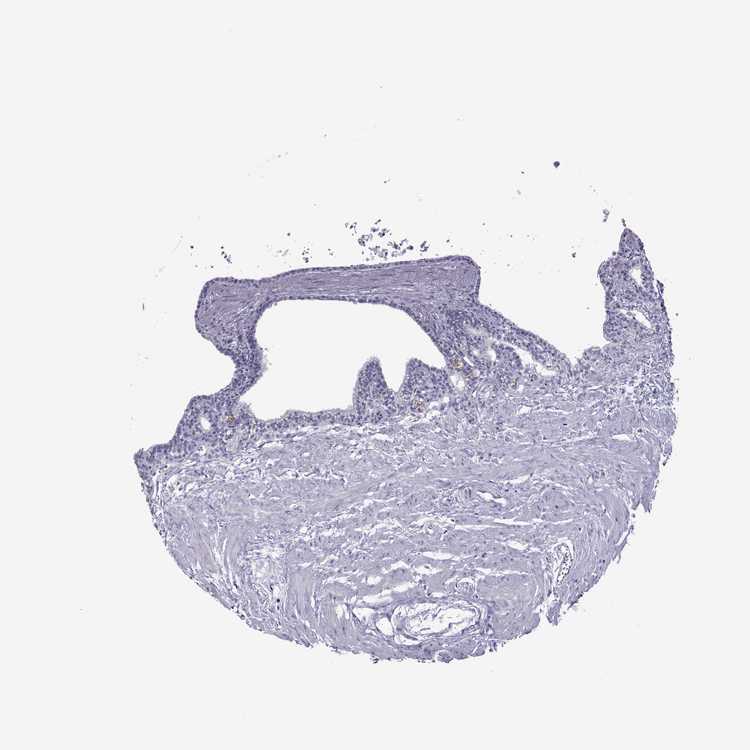

TISSUE PRIMARY DATA SEMINAL VESICLE Show tissue menu

SEMINAL VESICLE - Antibody stainingi

Antibody staining in the annotated cell types in the current human tissue is reported as not detected, low, medium, or high, based on conventional immunohistochemistry profiling in selected tissues. This score is based on the combination of the staining intensity and fraction of stained cells.

Each image is clickable and will lead to virtual microscopy that enables deeper exploration of all samples and also displays staining intensity scores, fraction scores and subcellular localization as well as patient and tissue information for each sample.

Antibody HPA039081Antibody HPA039082

Glandular cells Not detectedNot detected

Male, age 68

Seminal vesicle sample 386

nTPM: 1.1

Cell types%

Glandular cells:

20

Smooth muscle cells:

75

Other cell types:

5

overview

Male, age 70

Seminal vesicle sample 404

nTPM: 0.9

25

65

10

Male, age 67

Seminal vesicle sample 409

nTPM: 1

70